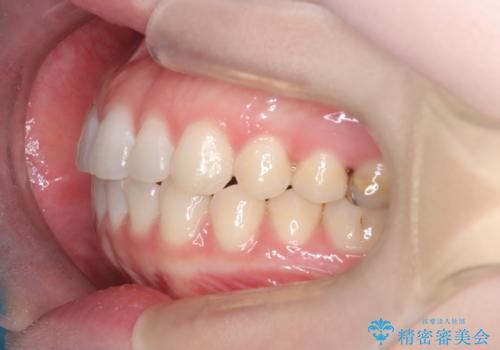

審美ワイヤー矯正とTAD併用による犬歯の遠心移動

- 歯並びの乱れを改善したいと来院されました。精密検査の結果、犬歯を奥へ動かすことで、より美しい口元と安定した咬み合わせが得られると診断。患者様のご希望から、目立ちにくい審美ワイヤー矯正を採用し、効率的な歯の移動のために**リンガルアーチとTAD(矯正用アンカースクリュー)**を併用する計画を立てました。これにより、抜歯せずにスペースを確保し、犬歯をスムーズに遠心へ移動させます。

今回の矯正では、装置が目立たないよう透明なブラケットと白いワイヤーを使用。さらに、効率的な歯の移動のために、歯の裏側にリンガルアーチを設置しました。また、確実な奥歯の移動のために**TAD(矯正用アンカースクリュー)**を一時的に使用。これにより、犬歯を狙った位置へ正確に動かすことが可能に。目立ちにくい装置で快適に過ごしながら、理想的な歯並びと咬み合わせを獲得していただけました。